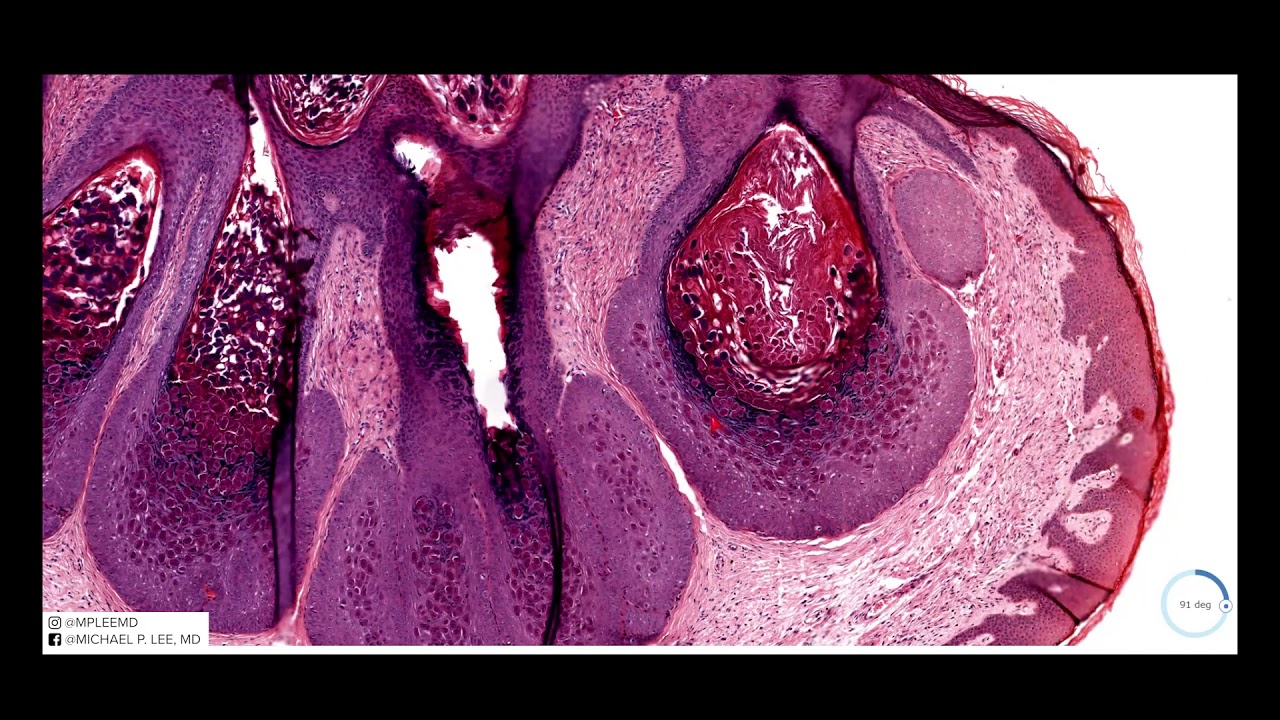

Myrmecia vs Molloscum. Dermpath Made Easy. Viral Video.

Описание: Case A. Myrmecia: HPV-1, acral/palmoplantar wart with anthill like appearance clinically. Endo (downward-growing) exophytic (outward growing).

Clue to DX: Coarse red cytoplasmic inclusions. All other features that are commonly seen in warts - i.e., hypergranulosis with coarse keratohyalin granules - are usually present. Nuclei retain's size or is often larger than the nuclei in normal skin.

B. Molluscum: Molluscum Contagiosum poxvirus. Multiple skin-colored to pink papules. An endophytic (downward growing) / cup-shaped and well circumscribed often with a scalloped border.

Clue to DX: The characteristic inclusions (Henderson-Patterson bodies or molluscum bodies), are very large and red to dark purple and take up most of the cytoplasm. They are so big that they displace the nuclei to the edge of the cell. They often like to hide in hair follicle epithelium if epithelia disrupted (by trying to squeeze a "pimple") a robust inflammatory tissue reaction.